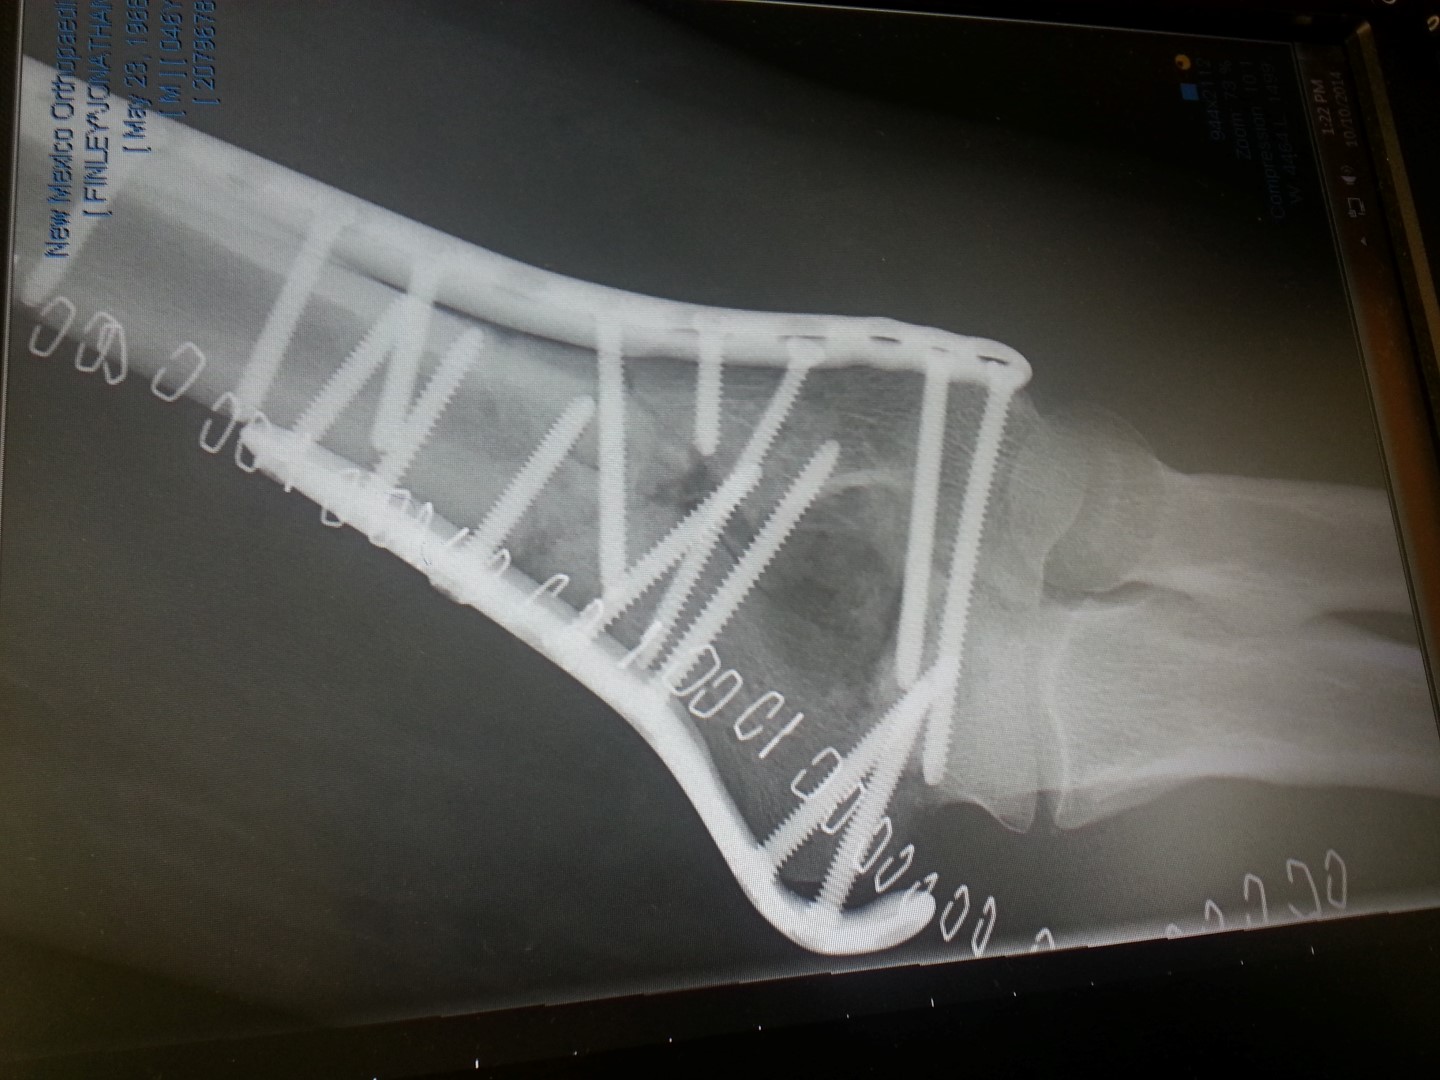

I’ve scheduled this post to magically appear on Thursday, April 28, 2016 on which I will once again be at the hospital having yet another surgery on my arm.

A check up last week, about a month after the last surgery revealed an issue that the doctor did not like so we are back at it again. Sadly, this one sounds like it may prevent much cycling this summer which is a huge disappointment. This whole “speed bump” adventure is now approaching two full years. Who would’a thought…